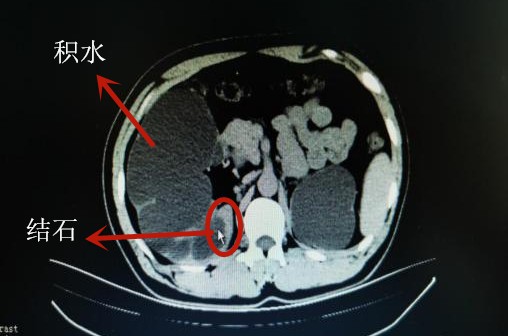

5年前,申先生在婚检时发现双肾有几颗细小结石,因没症状,一直没去治疗。一个月前,申先生因腰痛来院检查时,才发现双肾多发结石、重度积水,特别是左肾肾盂扩张积液、正常实质受压变薄,导致左肾功能基本丧失,右肾也有功能受损。如不尽快手术治疗,有可能右肾都保不住。

以泌尿四科主任杨科为首的医疗团队经术前讨论后,决定为其进行左侧输尿管钬激光碎石取石术和右侧经皮肾镜钬激光碎石取石术。术后,双肾结石引起的梗阻积水成功解决,但由于双肾积水时间太长,左肾功能完全丧失,而右肾也有20%的功能受损。